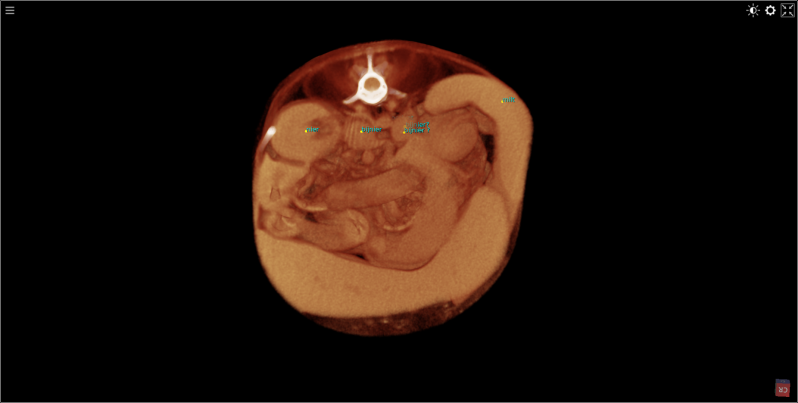

keeshond van 5 maanden met een  ernstige patella luxatie . De knieschijf zit permanent aan de binnenzijde van de knie. Het onderbeen heeft een torsie van 58.1 graden ten opzichte van het bovenbeen. Het bovenbeen heeft een kanteling van 29 graden ten opzichte van het kniegewricht.

De scan beelden zijn gebruikt om een operatieve ingreep voor te bereiden.